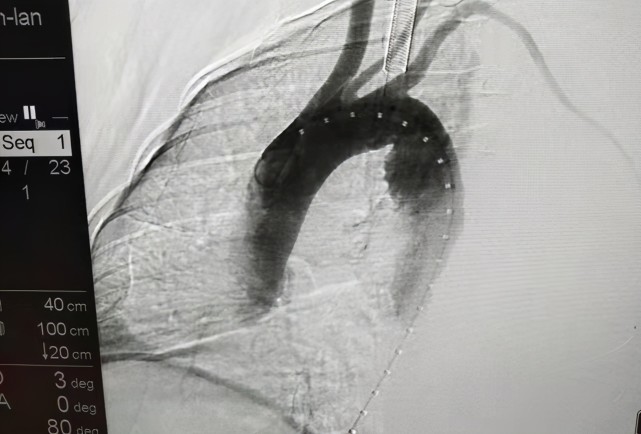

马凡氏综合征患者猝死的主要原因便是其心血管系统往往受到累及,常见的包括先天性血管畸形、主动脉扩张及心脏瓣膜关闭不全。

工作不久后便遇到了一例升主动脉瘤扩张破裂的病人,她的那一声“惨叫”至今记忆犹新,这种升主动脉瘤的破裂往往病情危急,即使在医院有时都来不及治疗。

当确诊马凡氏综合征后,及时行胸腹主动脉检查明确病变部位及程度,对于主动脉根部瘤样扩张、主动脉夹层的患者可通过外科手术干预,及时解除体内的“定时炸弹”。